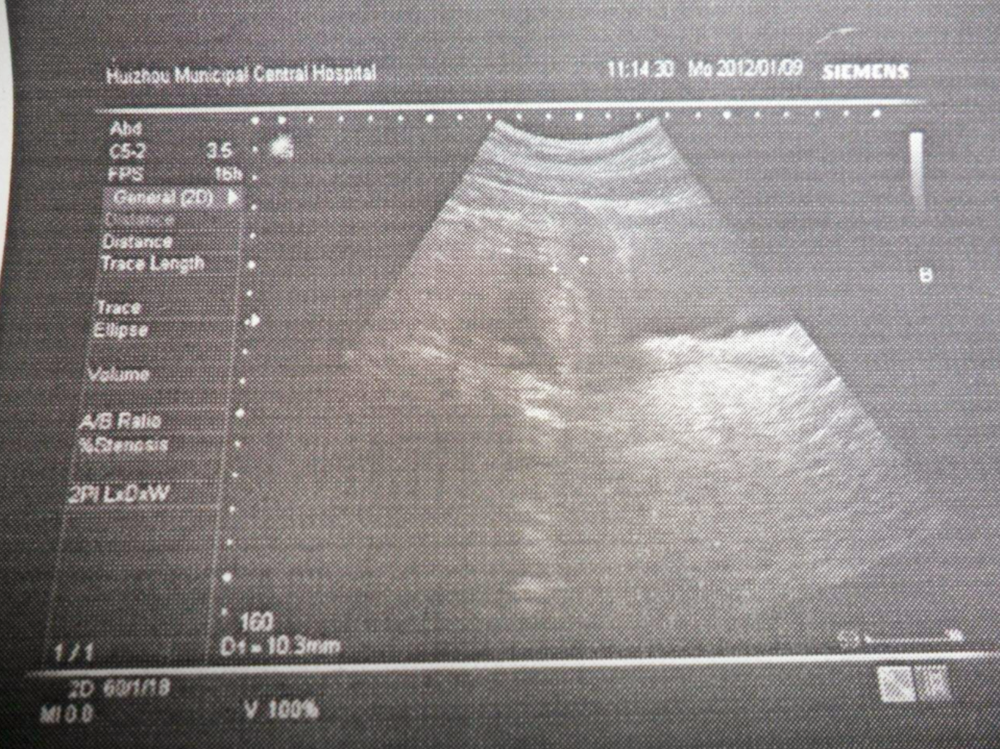

初次B超的最佳时间,为停经的第7~8周,这个时间段主要检测是否存在宫外孕、宫内妊娠、孕囊大小的情况。

这次的时间最好卡在停经的11~13+6周的时间,此时胎儿的头臀高会发育到4.5~8.4cm。这次B超的检查重点是颈后透明层的厚度、鼻骨的生成与否。